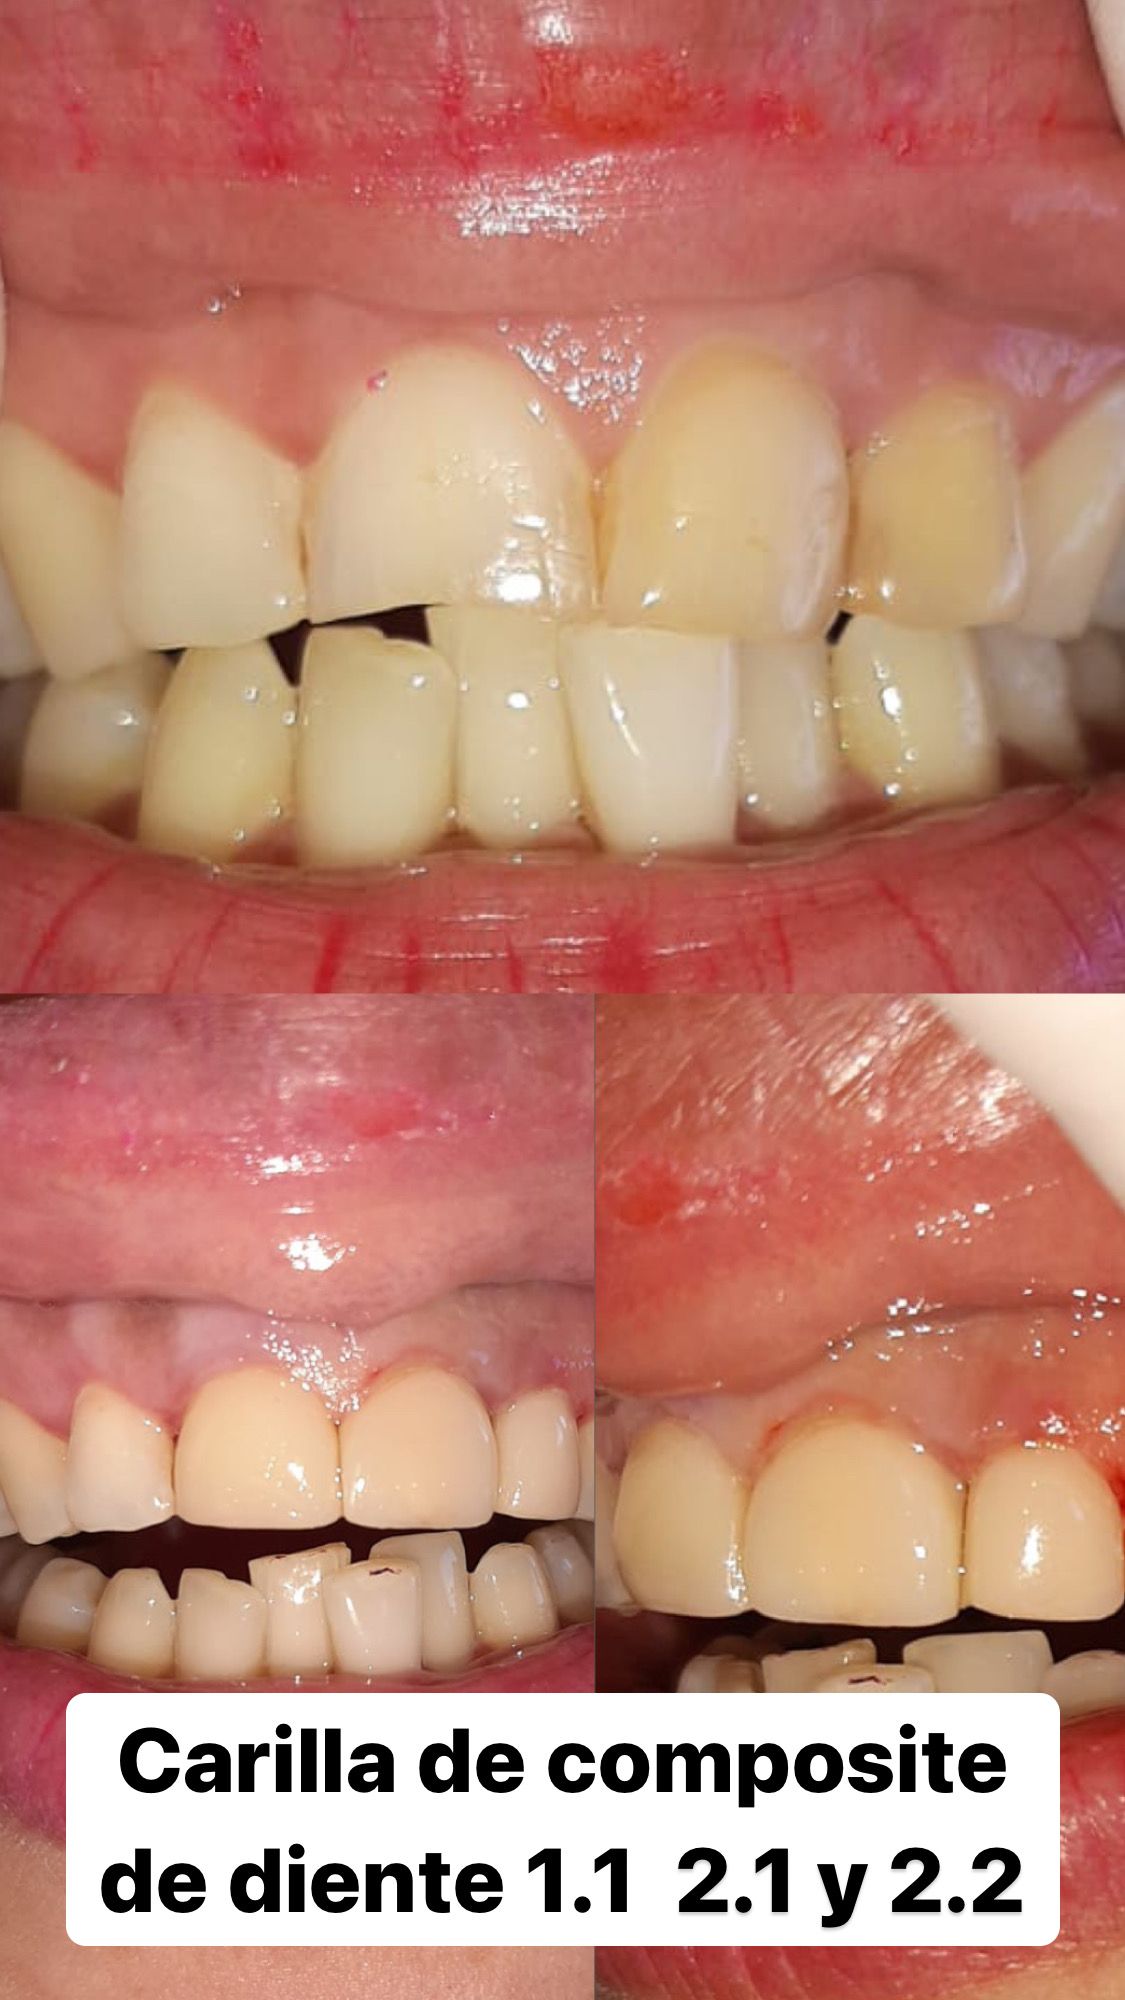

• Carillas de resina

Desde $250.000